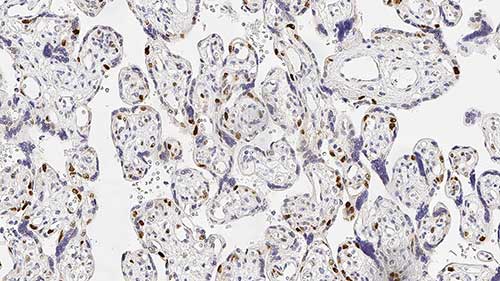

Transverse section of skeletal muscle fibers. Immunohistochemical staining for Alpha Sarcoglycan. Note the demonstration of localized Alpha Sarcoglycan to the sarcolemma of the muscle fibers. Alpha Sarcoglycan: clone Ad1/20A6

In normal skeletal muscle, dystrophin, the protein product of the gene which is defective in Duchenne and Becker muscular dystrophy, is attached to the muscle membrane via a complex of proteins (dystrophin-associated glycoproteins, DAGs). Dystrophin-deficient muscle shows a generalized reduction in DAG labeling. The expression of different members of the dystrophin glycoprotein complex is altered in several types of muscular dystrophy. For example, patients with LGMD2D have mutations in the gene for alpha-sarcoglycan, those with LGM2E have mutations in the beta-sarcoglycan gene, those with LGM2C have mutations in the gamma-sarcoglycan gene and those with LGM2F have mutations in the delta-sarcoglycan gene. As the sarcoglycans function together as a sub-complex, mutations in any one of the sarcoglycan genes usually results in variable expression for the whole group.